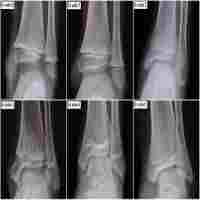

| Abstract | ObjectiveThis study aims to explore whether growth arrest lines can predict epiphyseal fracture healing.MethodThe data of 234 children with distal tibial epiphysis fractures treated in our hospital from February 2014 to February 2022 were retrospectively analyzed. Imaging data were examined to record epiphyseal grade, fracture type, and the time to appearance of growth arrest lines. Follow-up data were retrieved to record treatment results (i.e., malunion, premature closure, or bone bridge formation).ResultsThere was a significant difference in the time to appearance of growth arrest lines between patients with epiphyseal grade 0–1 and grade 2–3 (P < 0.05) and between patients with normal healing and patients with a bone bridge (P < 0.05). Among patients with normal healing, there were no significant differences in the time to appearance of growth arrest lines between men and women and between patients with and without surgery (P > 0.05). There was a significant difference in the time to appearance of growth arrest lines between patients with different Salter–Harris fracture types (P < 0.05).ConclusionFor patients with epiphyseal grade 0–1, the time to appearance of growth arrest lines could be useful for predicting the treatment result of a distal tibial epiphyseal fracture. |